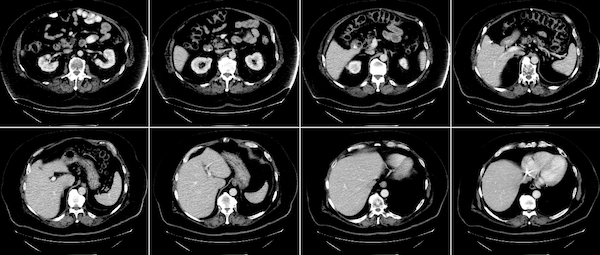

Gaussian mixturesmodule. This approach allows for dynamic optimisation according to the user-specified parameters and local system environments. The following figure shows results of MONAI’s Gaussian mixture models applied to tissue and surgical tools segmentation:

To easily visualize a 3D image as frames of 2D images, MONAI provides the utility matshow3d based on matplotlib library. It can plot frames of image for the specified dimension, showing a spleen 3D image as example:

matshow3d(volume=image, figsize=(100, 100), every_n=10, frame_dim=-1 show=True, cmap="gray")